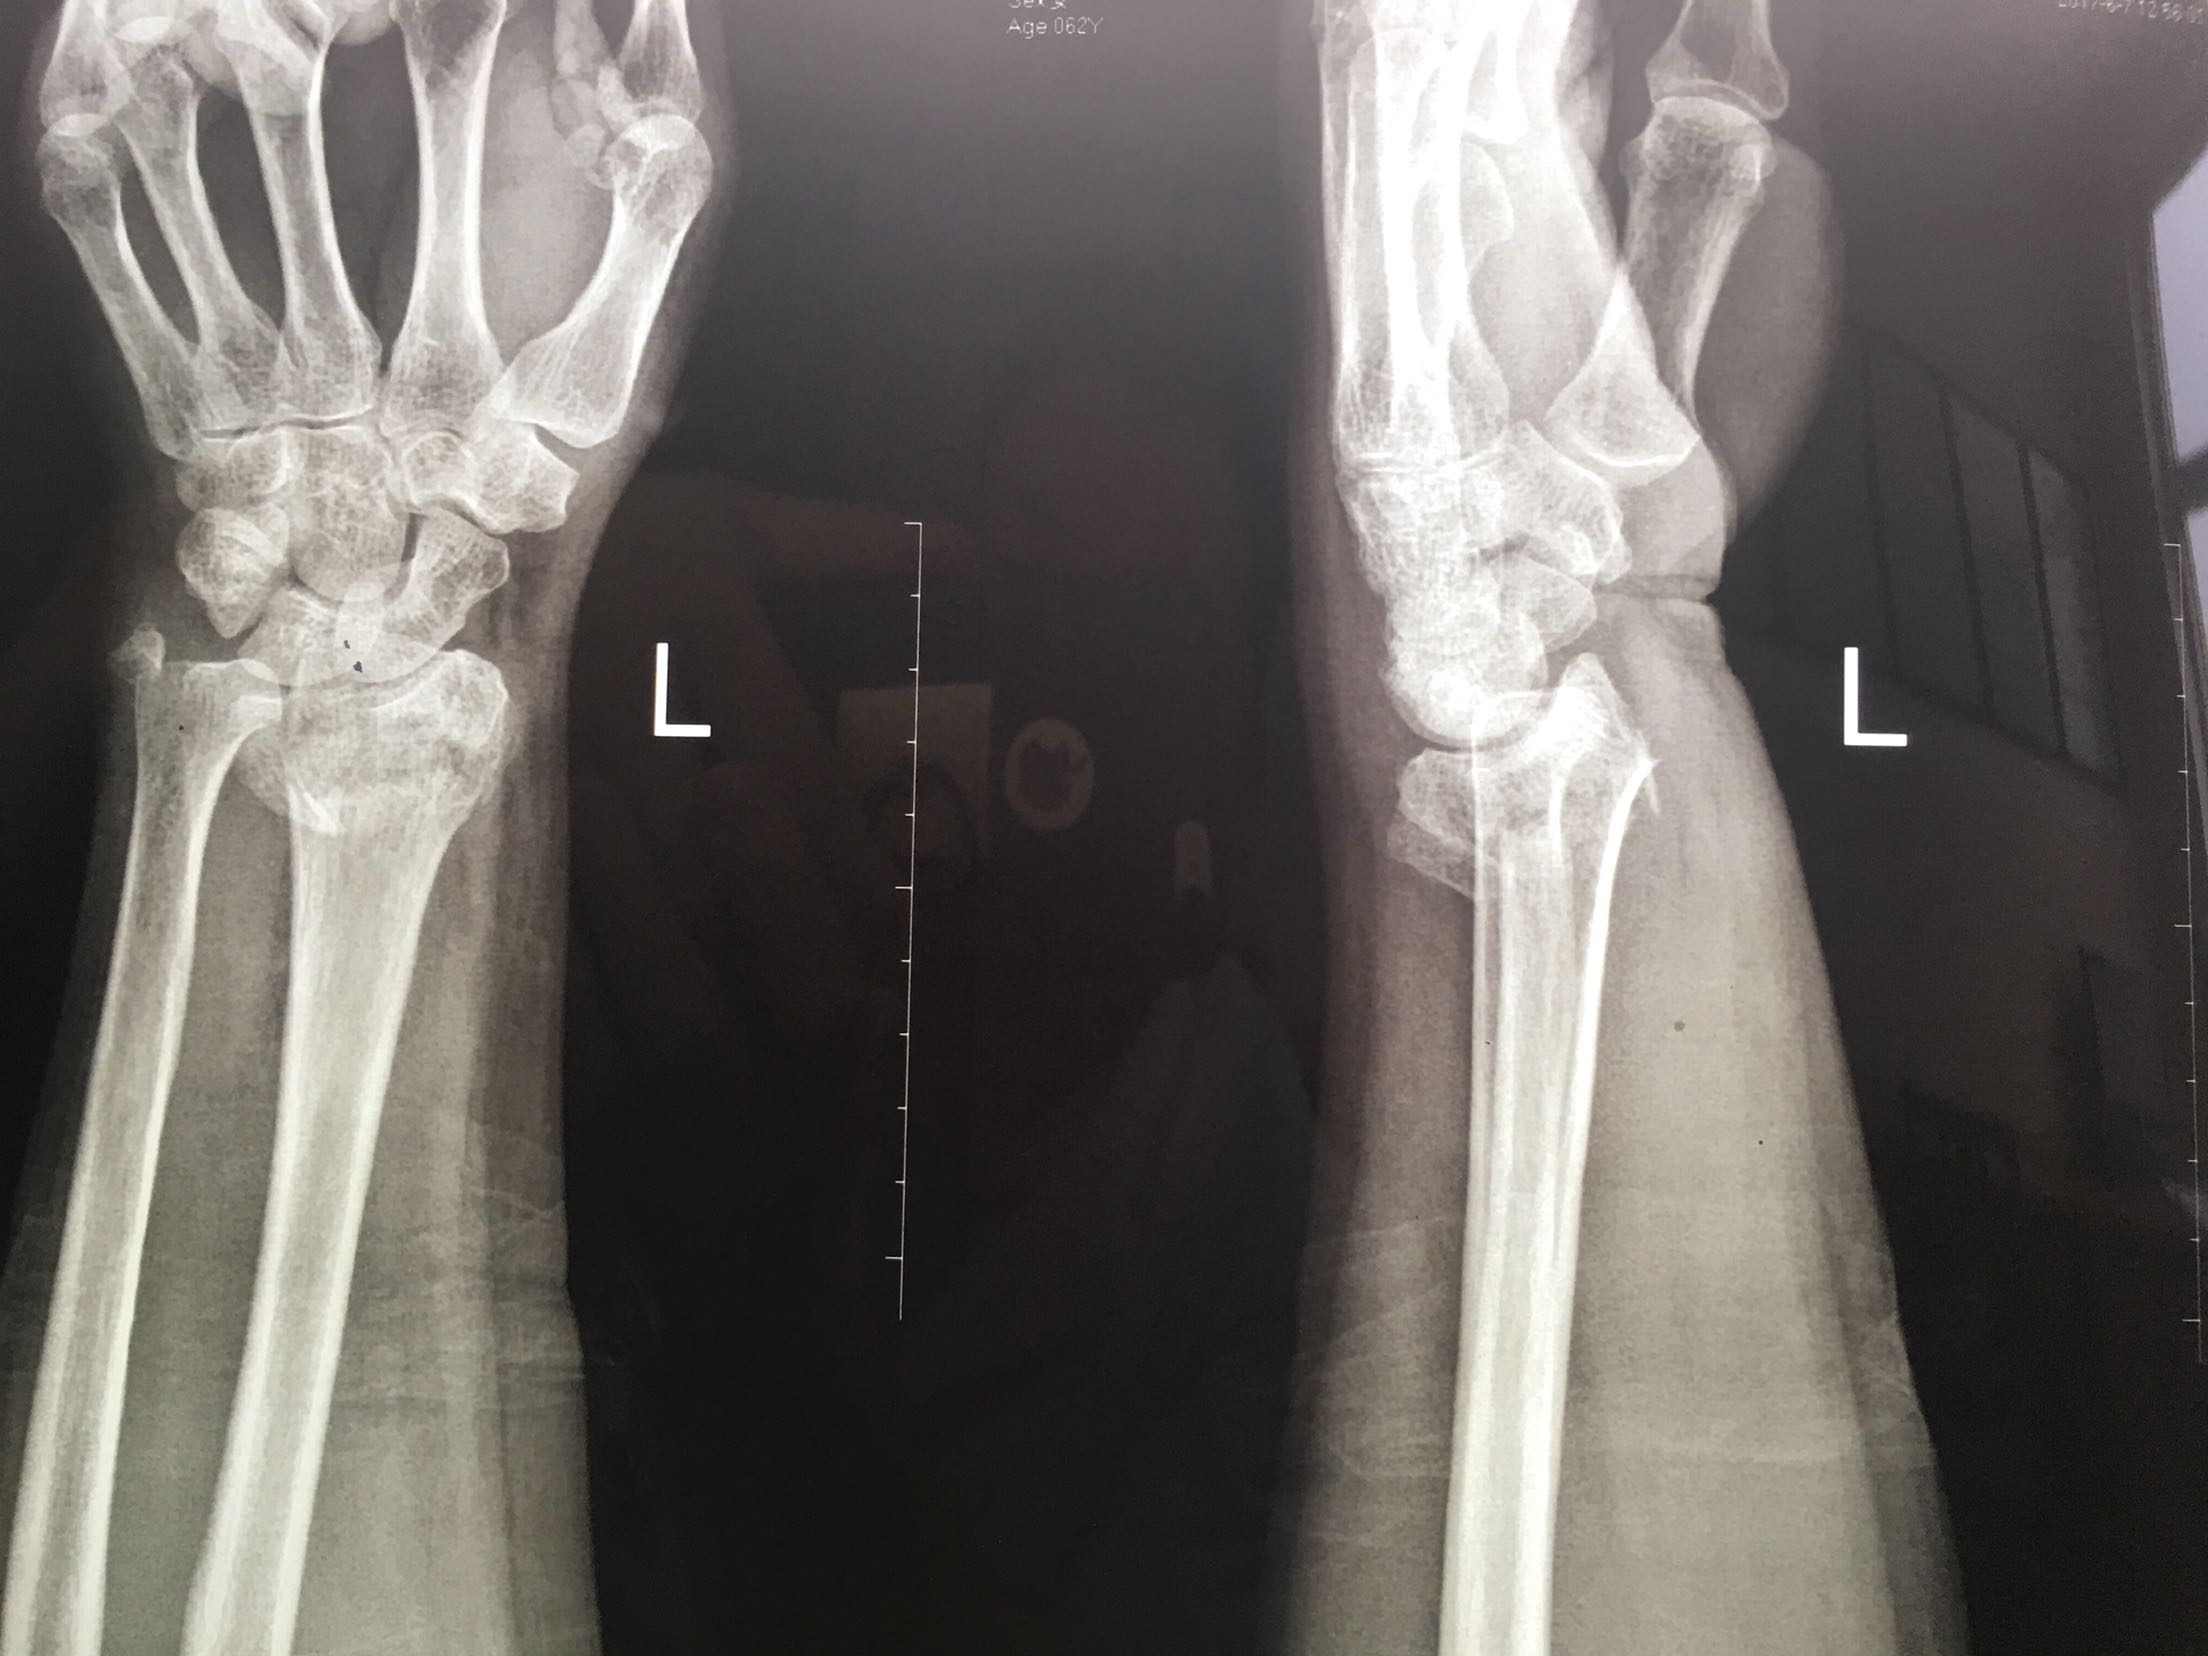

尺桡骨远端骨折

桡骨远端骨折尺骨茎骨折和下桡尺关节分离

桡骨远端骨折